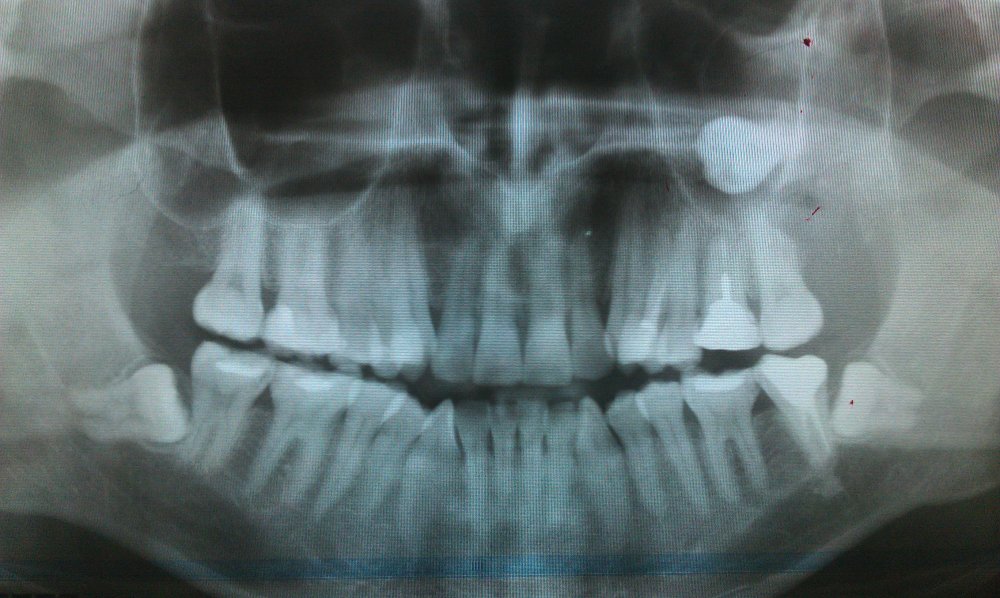

как правило коллеги с 30-40 летним опытом работы, стоматологов я имею ввиду, имеют и знания на уровне 30-40 лет назад. ибо учится чему-то новому не хотят и считают себя мега-звездами, что не мешает им творить всяческую хератень вроде такого убожества

Иллюстрация к комментарию